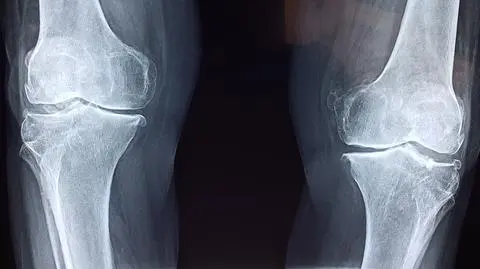

Naukowcy z Akademii Górniczo-Hutniczej w Krakowie pracują nad stworzeniem materiałów, które mogłyby zastąpić kości i wspomóc ich regenerację. Ponadto próbują zmusić je do walki z bakteriami. To duża szansa dla pacjentów z ubytkami.

"Sztuczna kość" szansą dla pacjentów z ubytkami

Kiedy dochodzi do ubytku kostnego na skutek wypadku czy interwencji chirurgicznej, nie zawsze jest on w stanie zregenerować się samoczynnie. Wówczas zostaje ograniczona sprawność pacjenta i normalne funkcjonowanie. Dzięki naukowcom z Akademii Górniczo-Hutniczej w Krakowie może się to zmienić. Od lat prowadzą oni bowiem badania nad innowacyjnymi materiałami stosowanymi do wypełniania ubytków.

Naukowcy AGH stale dążą do udoskonalenia technologii. Teraz skupiają się na granulach, które mogłyby być "sztuczną kością" i wypełnić uszkodzenia, a jednocześnie miałyby mieć działanie antybakteryjne.

- Prace nad materiałami kościozastępczymi skupiają się obecnie na połączeniu zalet związków syntetycznych oraz naturalnych, tworzących materiały hybrydowe. Bazę tych biomateriałów często stanowią fosforany (V) wapnia oraz materiały polimerowe. Tego typu materiały, odpowiednio zastosowane, mogą wspierać, a niejednokrotnie również indukować regenerację tkanki kostnej - argumentują autorzy.

Wytworzone przez naukowców granule są na tyle duże, że można je zobaczyć gołym okiem. Ich rozmiary sięgają od 100 mikrometrów (0.1 milimetra) do nawet 1000 mikrometrów (1 milimetra). Jak czytamy na stronie uczelni, badacze najczęściej wykorzystują granule z zakresu 300–400 mikrometrów, ale niewykluczone jest stosowanie innych rozmiarów. - Po umieszczeniu granul w ubytku kostnym będą one mogły stanowić rusztowanie dla odbudowującej się tkanki - podkreślają twórcy.